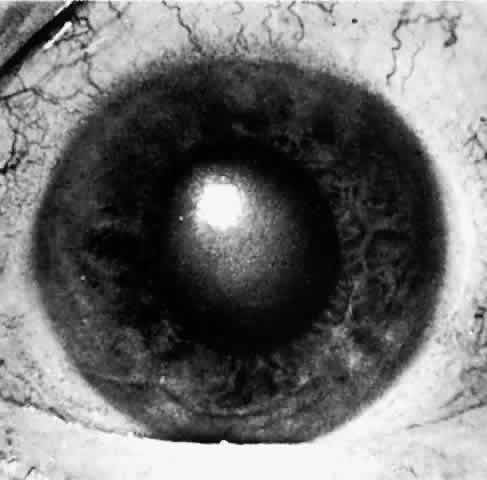

When a patient is seen after an attack that has been in progress for several hours or even days, the eye usually will display decreased vision. The pupil is irregular in shape, nonreactive to light, and resistant to the effects of miotics or mydriatics. It is a common misconception that the intraocular pressure remains elevated in angle-closure glaucoma. In some cases, low tension may be found after aqueous production has decreased while the angle remains closed. If the eye has recovered spontaneously from an attack, the intraocular pressure may be very low due to reduced aqueous formation with or without an open angle. It is important to realize that low pressure following elevated pressure due to acute angle-closure glaucoma does not necessarily mean that the angle-closure attack is over. The pressure will rise as soon as aqueous production resumes, which may be a few hours to many weeks later. The cornea may show Descemet's folds and later recover its transparency but occasionally the corneal edema may persist for weeks after reduction of intraocular pressure. A prolonged iris stromal edema encourages the formation of posterior synechiae in the pupillary area and peripheral anterior synechiae at the level of the angle structures. The destruction of iris tissue results in grayish patches of atrophic iris stroma that may extend to the periphery (Figs. 9 through 11). Tiny white-gray spots with discrete edges may be seen in the pupillary zone. These anterior subcapsular lenticular opacities, best known as glaukomflecken, appear to be the result of damage to the anterior lens epithelium from very high intraocular pressure (Fig. 12).35 Glaukomflecken may result from very high intraocular pressure of any etiology, but are especially characteristic of previous attacks of angle-closure glaucoma.